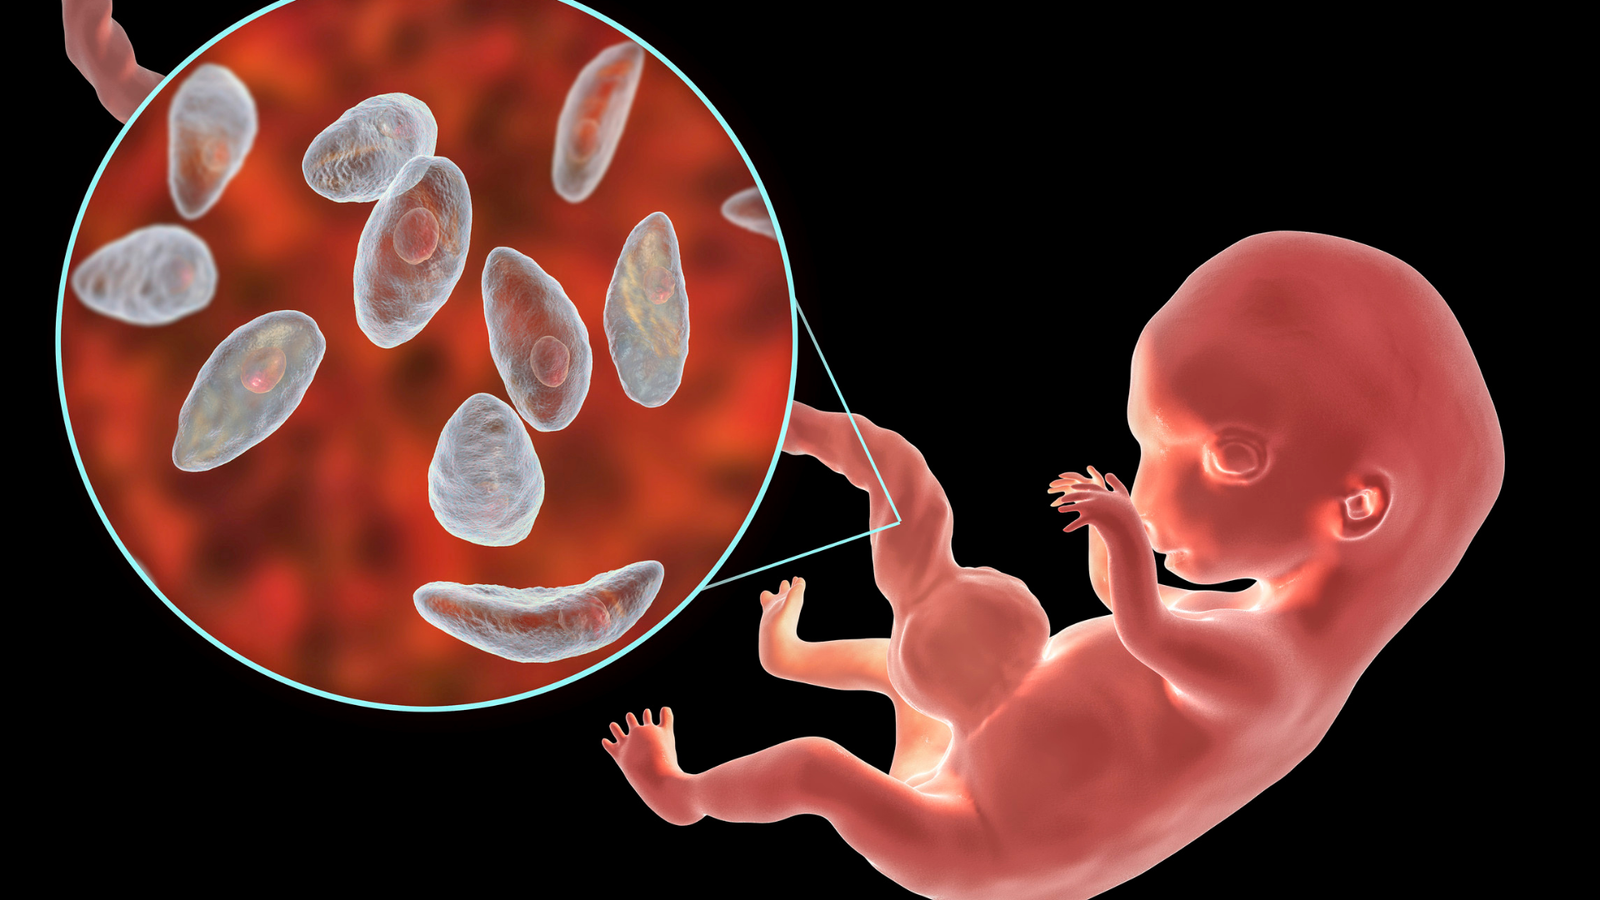

NGS Tedavisi (Next-Generation Sequencing) Gürcistan Tüp Bebek

NGS (Next-Generation Sequencing) Nedir? NGS (Next-Generation Sequencing), tüp bebek tedavisinde